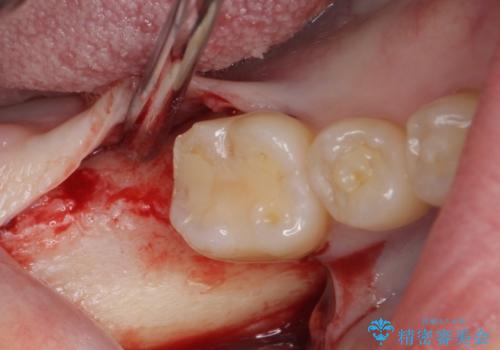

- 抜歯してから放置されている右下の奥歯へのインプラント治療を希望して来院された患者様です。

世界中で高い信頼を得ているストローマンインプラントを用いて治療を行うこととしました。

ストローマン社のSLActiveというインプラントを使用し、インプラント埋入からクラウンが装着されるまで3ヶ月弱という短期間で終えることができました。

- 外科手術のため、術後に痛みや腫れ、違和感を伴います